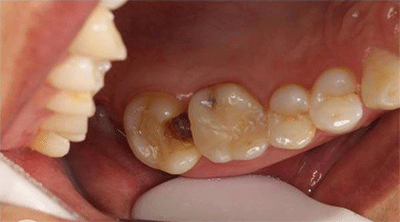

术前照

术前显微镜影像